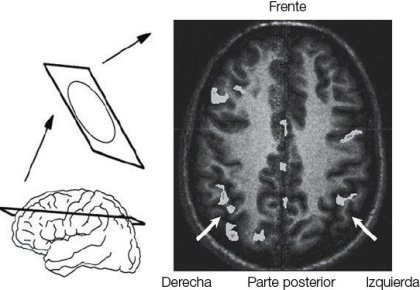

Tuve la suerte de comenzar a trabajar en este libro durante los primeros años de la década de 1990, en un momento en que la investigación sobre el número estaba dando los primeros pasos. Un puñado de laboratorios empezaba apenas a rozar el tema, inaugurando este campo de investigación. Algunos hacían foco sobre cómo los niños percibían conjuntos de objetos. Otros se especializaban en la forma en que los niños en edad escolar aprenden las tablas de multiplicar, o estudiaban el extraño comportamiento de los pacientes que sufren lesiones cerebrales que alteran las habilidades para el cálculo. Por último, algunos —entre ellos, yo— hacían las primeras incursiones en la investigación en neuroimágenes para descubrir qué áreas cerebrales se activan cuando a los estudiantes se les hace una pregunta aritmética sencilla, como « ¿6 es más grande que 5?». En ese momento, solo unos pocos de nosotros podíamos ver que todos estos estudios un día confluirían en un solo campo, la cognición matemática, con una serie de técnicas multifacéticas que apuntaban a responder a la estimulante pregunta de Warren McCulloch:

Desde que se escribió este libro, cerca de quince años atrás, un frenesí de investigación innovadora ha dado a esta área un ímpetu más fuerte que el que nunca imaginé. La cognición matemática es hoy un campo importante de la ciencia cognitiva, y ya no se centra exclusivamente en el concepto del número y sus orígenes, sino que se ha expandido a los campos relacionados del álgebra y la geometría. Varios temas de investigación que fueron apenas esbozados en este libro se han convertido en áreas de investigación por derecho propio: el sentido numérico en los animales, neuroimágenes de cómputos matemáticos, la naturaleza de la discalculia (el déficit en los niños que tienen dificultades matemáticas), etc. Uno de los logros más emocionantes ha sido el descubrimiento de neuronas independientes que codifican el número en el cerebro del mono, en una localización precisa en el lóbulo parietal, que parece ser un homólogo plausible de las regiones corticales que se activan cuando hacemos cálculos mentales. Otra corriente de investigaciones en constante y veloz desarrollo está relacionada con la aplicación de este conocimiento a la educación: ya empezamos a comprender cómo la escuela desarrolla un sentido exacto del número y la aritmética, y cómo se puede ayudar con juegos y programas informáticos pedagógicos muy simples a los niños que están en riesgo de desarrollar discalculia.